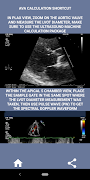

На мой взгляд, если собеседник может убедительно продемонстрировать этот навык, у него будет огромное преимущество перед другими кандидатами, которые слабы в этой области (это логично, поскольку обычно бывает так много случаев стеноза аорты). Если вы подаете заявку на должность кардиолога-сонографиста, кого-то, кому просто нужно освежить свои навыки, или студента эхолокации, то это приложение было разработано специально для вас практикующим кардиологом-сонографом. Простой и краткий, подходящий к делу, со множеством иллюстративных видеороликов, указывающих, где именно измерять (например, диаметр LVOT) и как проводить измерения в соответствии с опубликованными руководящими принципами ASE / ICAEL.